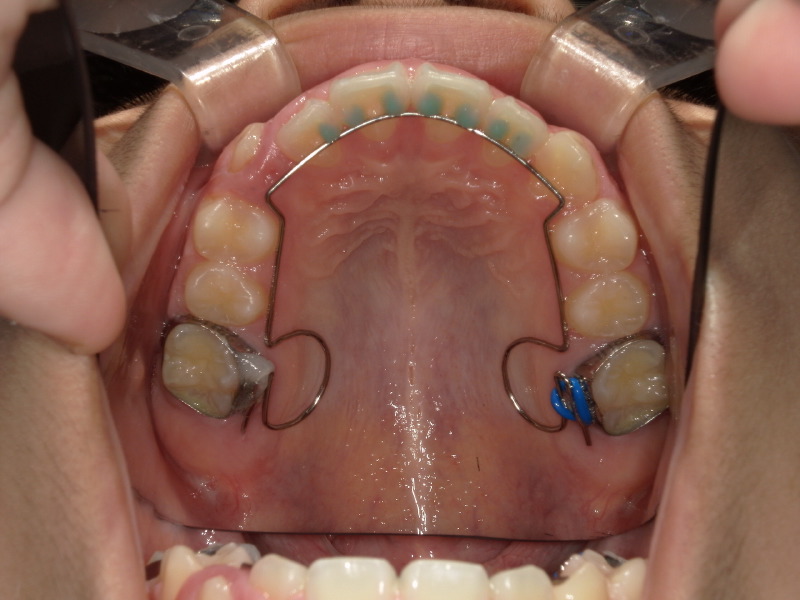

BWSの装着

アクティビティーも順調に進み、次は八重歯の歯を綺麗に入れるために装置を併用することになりました。

装置装着日 3ヶ月後

少しずつ入れる余裕が出てきています。

この間もマウスピース、アクティビティーは継続しています。

一時的に顎の中に装置が入りますが上顎なのでそこまで見えたり気になることはないです。

装置をもう少し併用したかったのでタイミングをみて再度型取りをしました。

装置をつけた日と外した後、外してから3ヶ月後の写真です。

八重歯だった歯はしっかりとアーチの中に入っていて綺麗になりました。